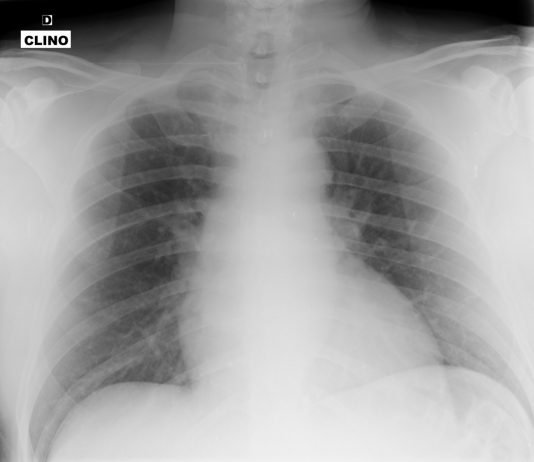

49-year-old male

patient admitted to the ED with fever (39°C) and...